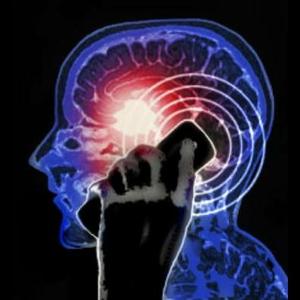

آسیب های مغزی